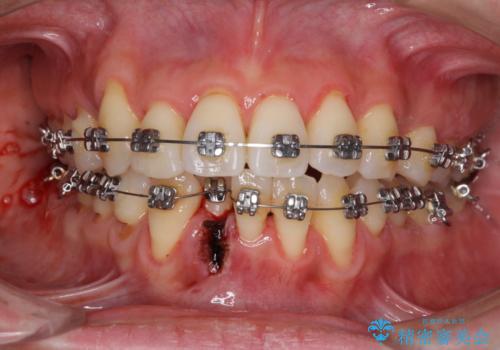

通常であれば、上下顎左右小臼歯各1歯の合計4本を抜歯しますが、歯肉退縮の著しい下顎前歯を抜歯して欲しいという患者様の強い希望により、上顎のみ左右小臼歯2歯を、下顎は前歯を1歯を抜歯することとしました。

抜歯する歯を変更したため奥歯の咬合はアンバランスとなりましたが、前歯は綺麗に整い、歯肉退縮も回避できました。